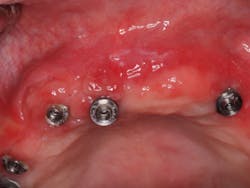

One of the most important steps that you can take to improve the chances of patients adequately maintaining their oral hygiene is to set up your plan for success from the beginning. Patients are often referred to my practice with complications after the delivery of their final prosthesis. A common origin of these complications is inadequate vertical height for the bridge. Aside from this resulting in fractures of the bridge, it is also the primary source of creating a concave intaglio surface (figure 2).

Figure 2: Concave intaglio = hygiene nightmare

The patient whose bridge is shown in Figure 2 returned to her dentist after the final bridge was placed complaining of speech difficulty and pain. The dentist told her everything was normal and that she needed to adapt to the bridge. Three months later, the patient presented to my office. The speech issue was legitimate in my opinion (that’s a story for another day), but I was concerned about the sensation of pain.

I removed the bridge to find the intaglio packed with food debris. The patient’s tissue was inflamed (figure 3), and she had developed a fungal infection. This could have been avoided with better presurgical preparation, adequate bone reduction, and proper vertical space development, which would have allowed the lab to make a hygienic intaglio (figure 4). Note the smooth and flowing intaglio surface in Figure 4. This is a bridge that can be easily maintained by the patient and hygienist.

Figure 3: Inflamed tissue from an inability to clean under the bridge